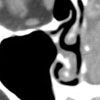

DISCUSSION: A facial CT scan showed opacification of the maxillary, ethmoidal, and sphenoidal sinuses, consistent with a left paranasal sinus mass (Figure). The mass caused destruction of the bony architecture of the left inferior and medial nasal turbinates with extension into the nasopharynx.

In this patient, CT scans of the head, neck, chest, abdomen, and pelvis as well as MRI scans of the head and neck showed no evidence of metastasis. She is currently undergoing radiotherapy and chemotherapy.